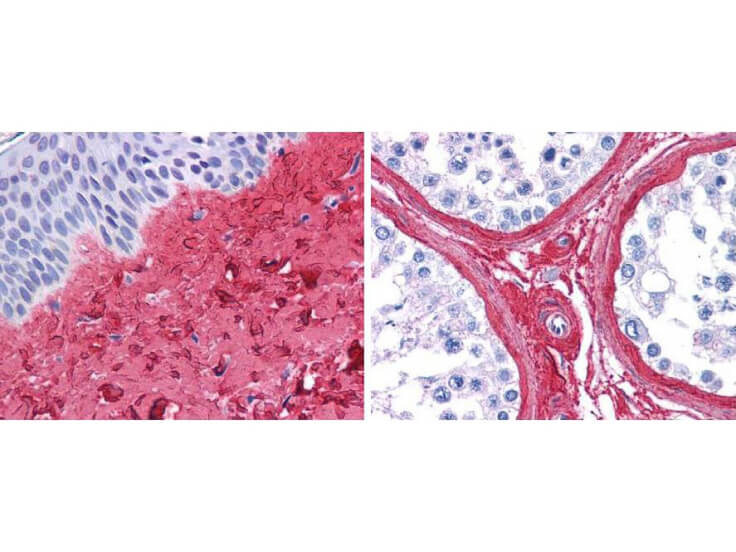

Rockland's Obesity & Diabetes category offers a specialized selection of primary antibodies aimed at identifying shared molecular targets associated with both conditions. These high-quality antibodies are essential for research into the common pathways and mechanisms underlying obesity and diabetes, providing reliable tools for advanced experimental studies.